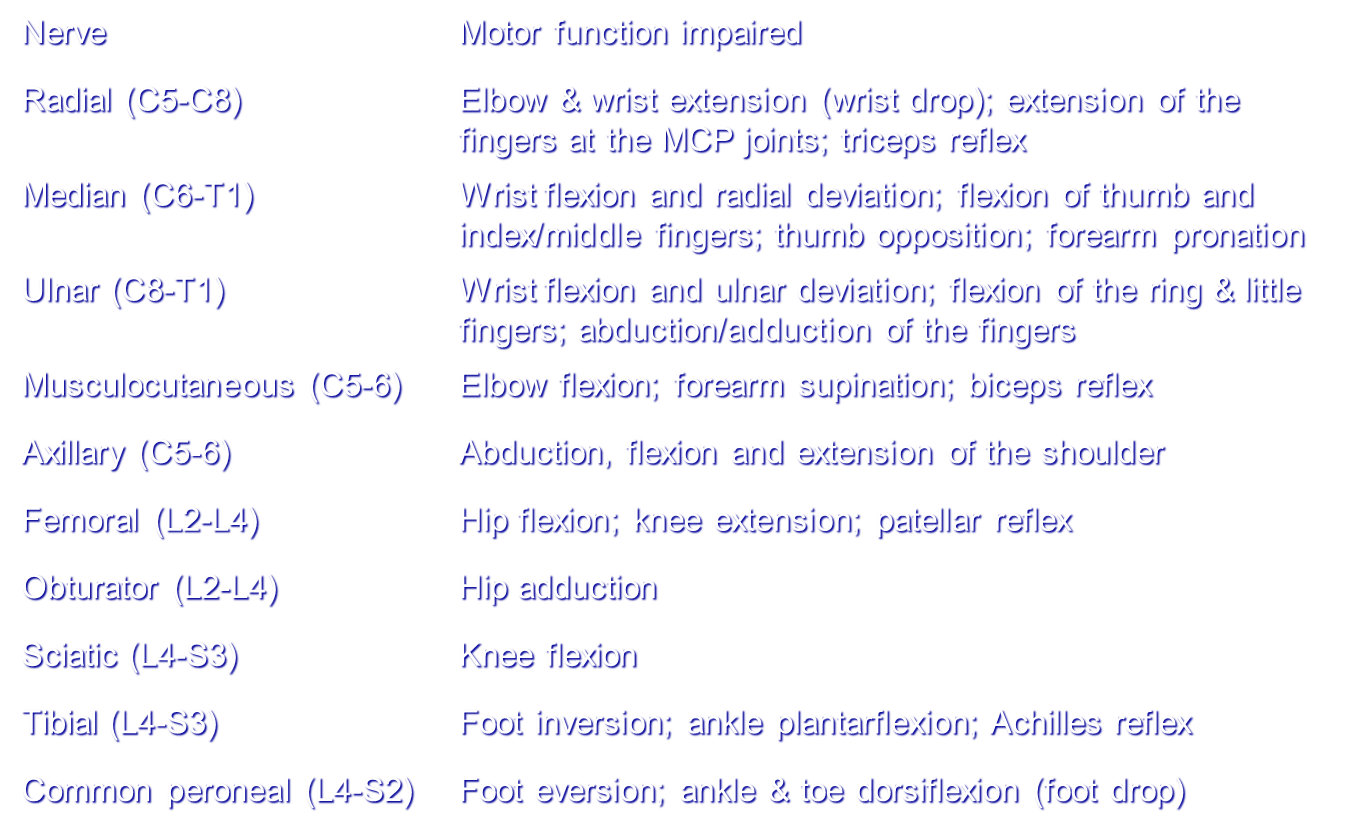

Peripheral Nerve Injuries